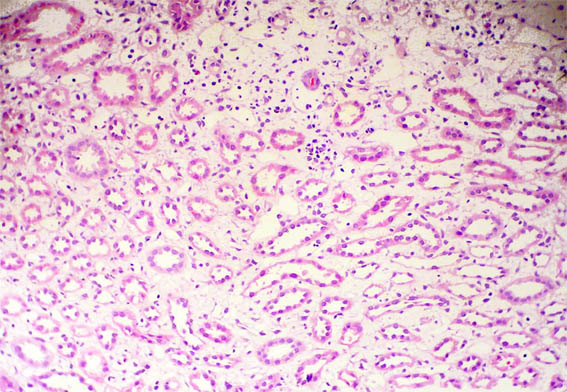

Figura 1.

H&E, X100.